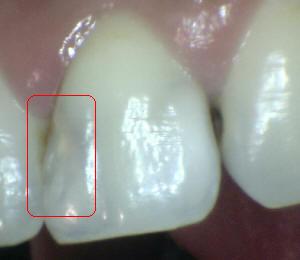

Sistema Internacional para la Detección y Evaluación de Caries (ICDAS)

¿Determine los códigos pertinentes a cada imagen?

Click en el hipervínculo: Para comparar el resultado de su diagnóstico